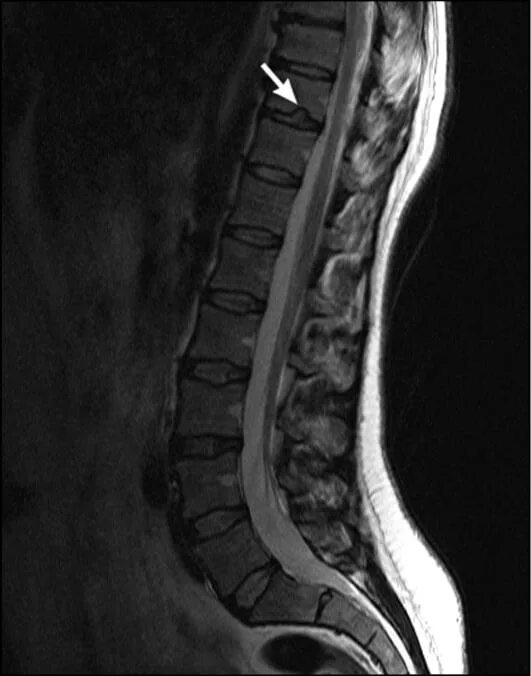

Грыжа шморля протрузия